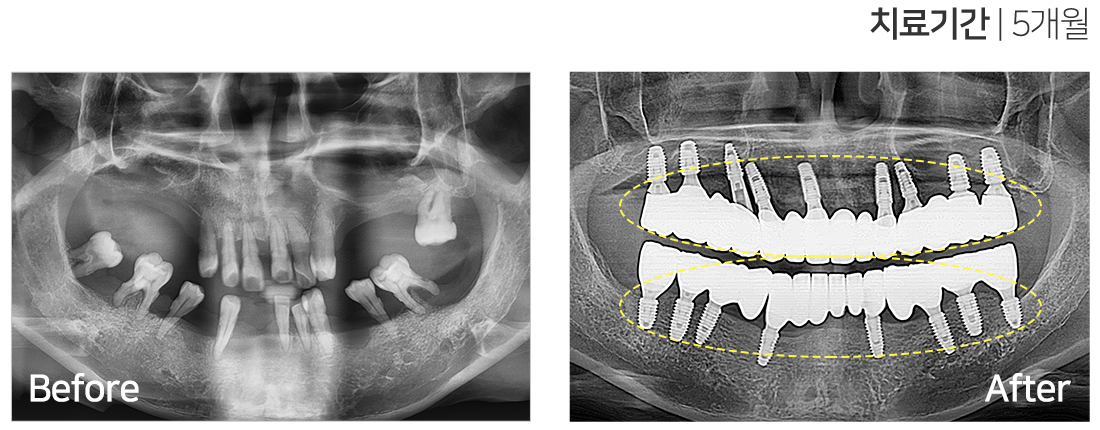

임플란트 시술 사례

풀아치 임플란트

IMPLANT TREATMENT CASES

※ 전신질환 및 관리 능력에 따라 임플란트 주위염 등의 부작용이 있을 수 있습니다.